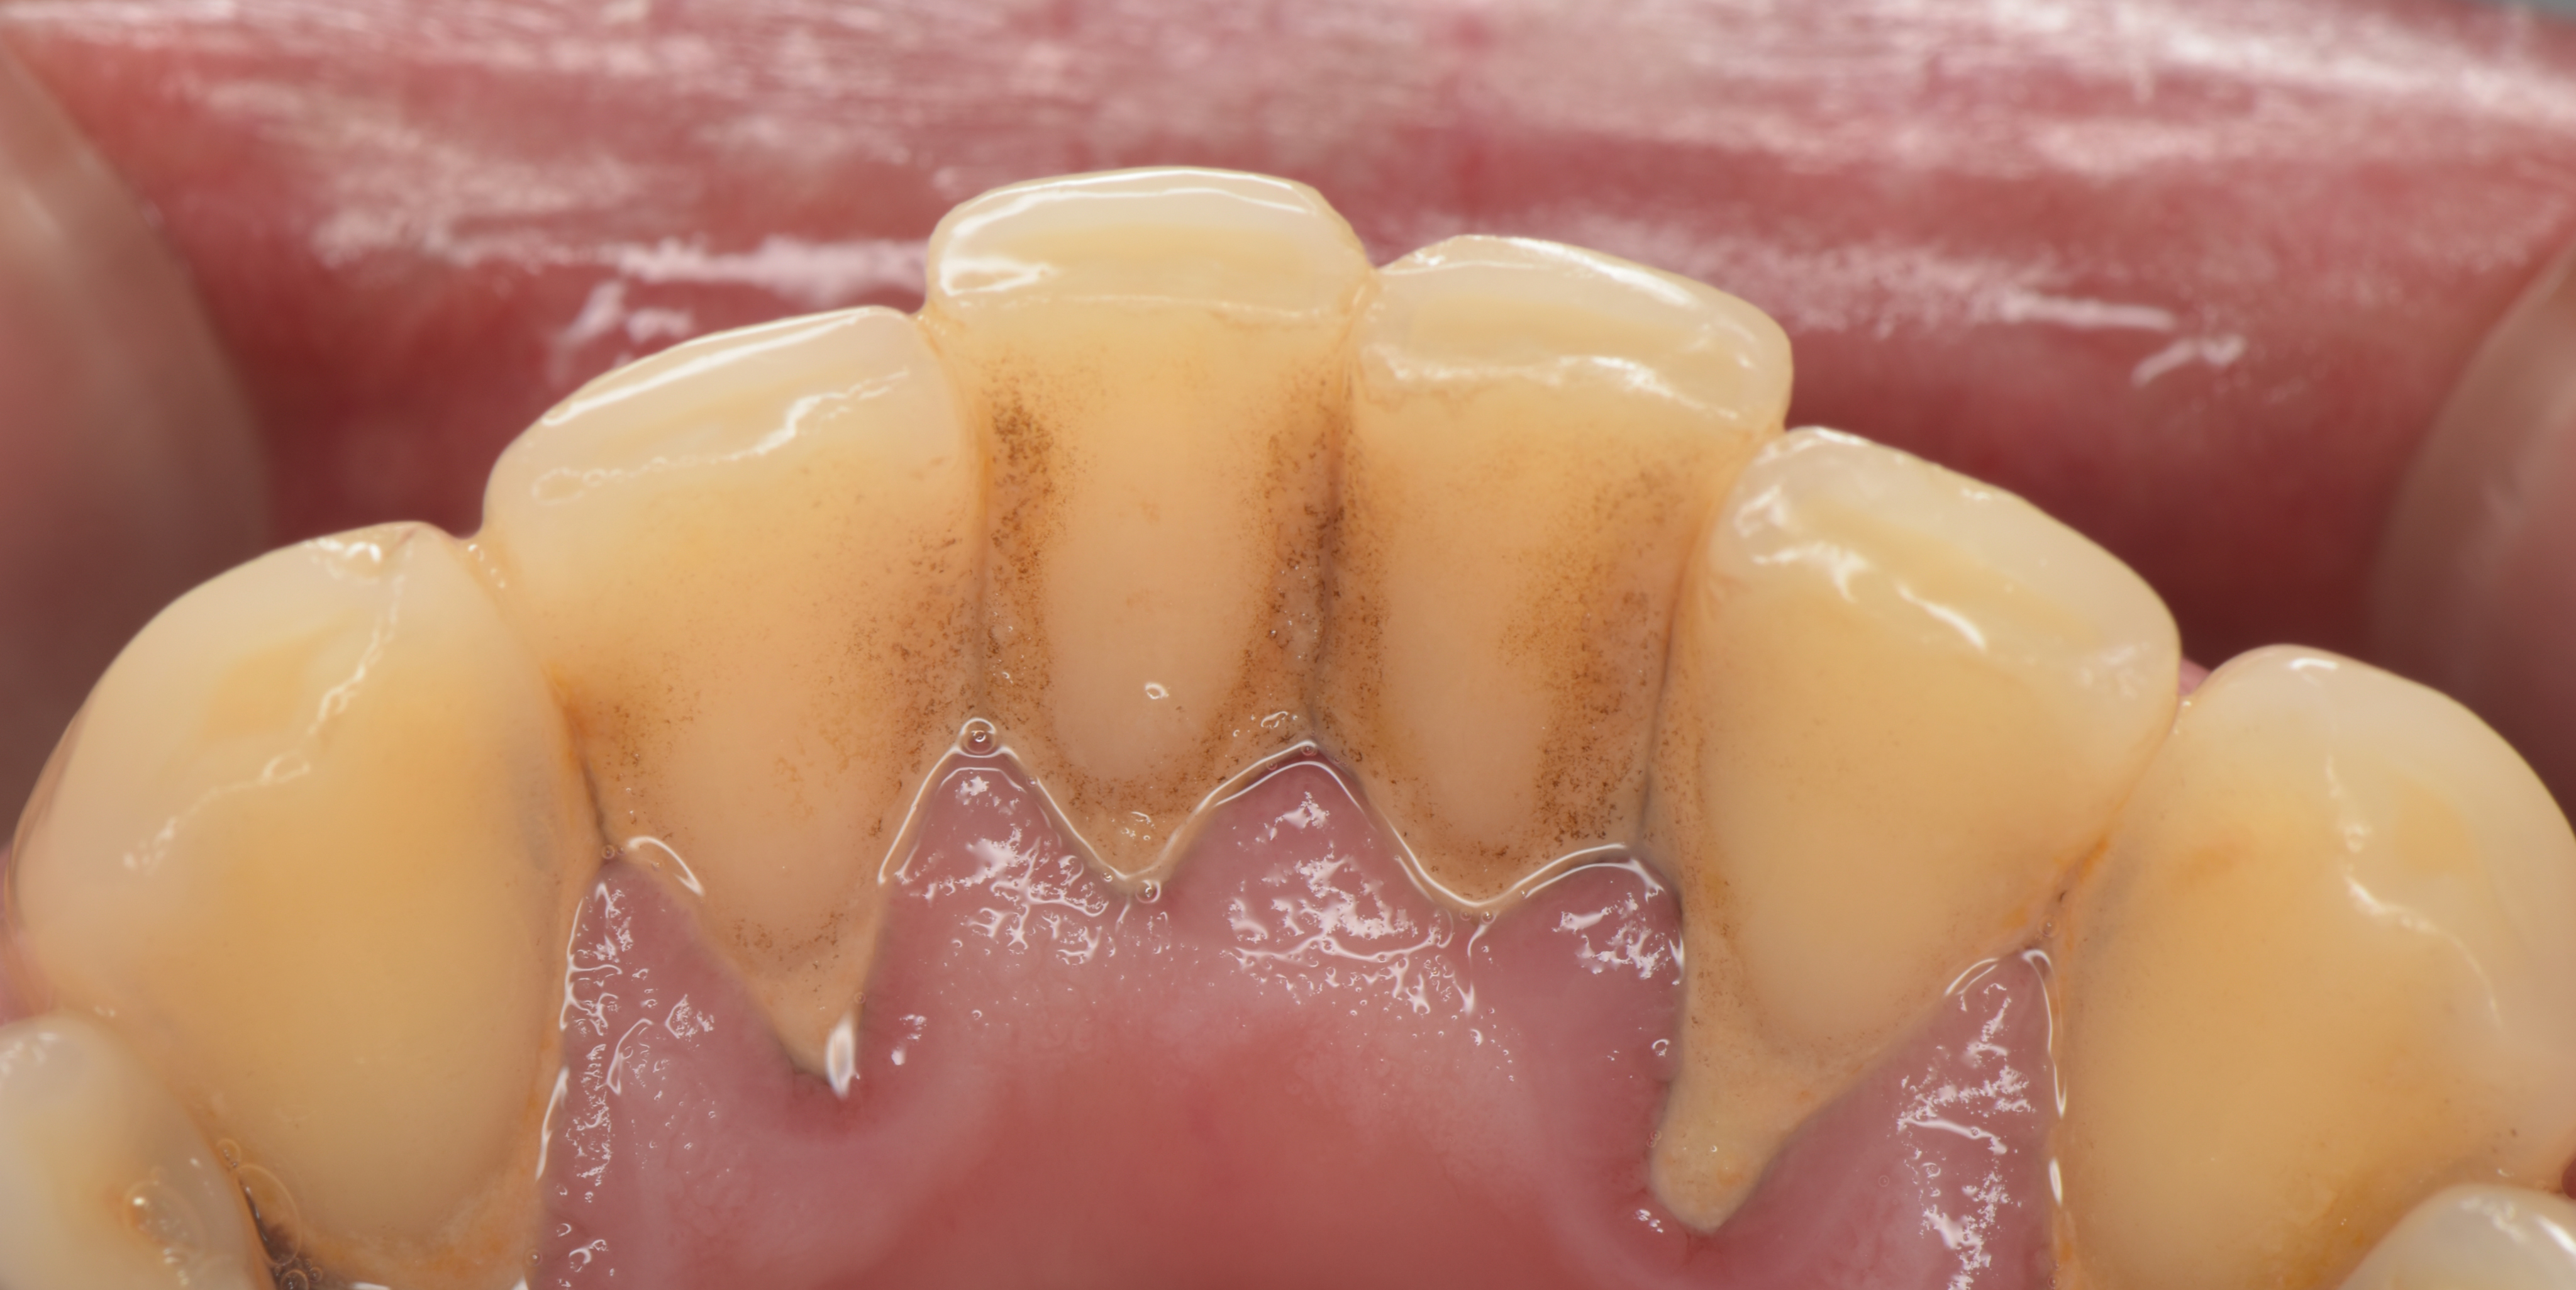

歯石付着している状態

一年ほどでここまで歯石が付着する場合もあります。